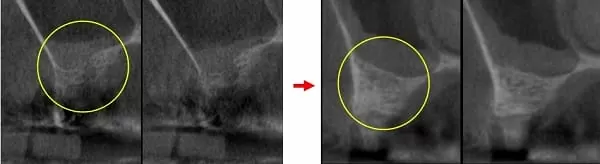

斷層顯示第一小臼齒外側骨頭已破洞 → 大臼齒區已經沒有骨頭,像蛋殼一樣薄

治療前:第5顆缺牙處,骨高度約2mm → 治療後:鼻竇增高至10mm

治療前:第6顆缺牙處,骨高度約1mm → 治療後:鼻竇增高至9-12mm

治療前:鼻竇非常低 → 治療後:墊高鼻竇,填入大量骨粉